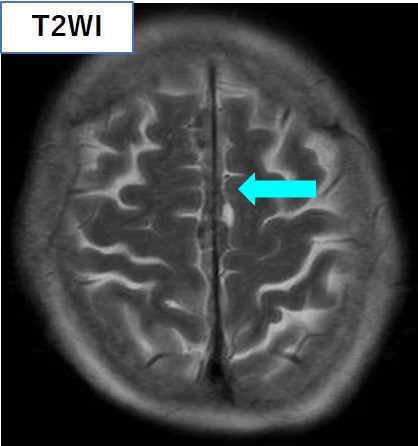

頭部CT・MRIにて、大脳鎌に沿った腫瘤を認め、左小脳橋角部にも腫瘤を認める。いずれもT1強調像で高信号、T2強調像で低信号を呈している。

頭部MRI

<中枢神経病変>

• 髄膜に沿った腫瘤形成(23%)

• 下垂体後葉のT1高信号が消失(47%)